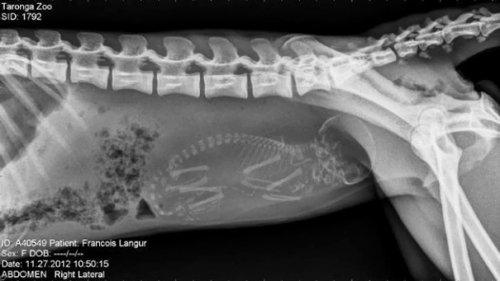

Итак, как выглядят рентгеновские снимки беременных животных:

лангур (обезьяна)